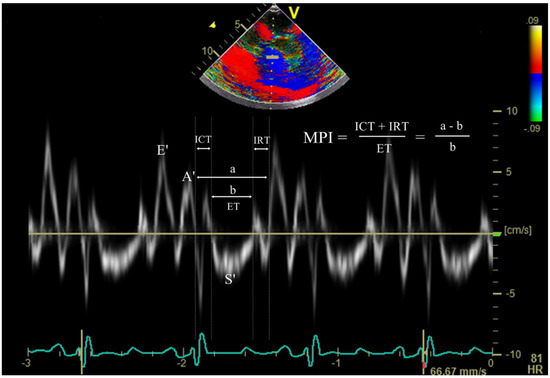

Hemodynamic variables obtained were the heart rate, mean arterial pressure, and central venous pressure. The echocardiographic assessment was conducted by a single anesthesiologist blinded to the experimental conditions using a single echocardiography system (Vivid E9; GE Vingmed Ultrasound AS) from mid-esophageal four-chamber view at the end of expiration. This assessment included the measurement of LV ejection fraction (LV EF), RV fractional area change (RV FAC), peak early diastolic velocities of septal mitral annulus and lateral tricuspid annulus (MV E′ and TV E′, respectively), late diastolic velocities of MV and TV (MV A′ and TV A′, respectively), peak systolic velocities (MV S′ and TV S′), and tricuspid annular plane systolic excursion (TAPSE). Peak early diastolic transvalvular inflow velocities (E) of MV and TV were also measured to calculate E/E′ for both ventricles. To measure the overall biventricular function, myocardial performance index (MPI) was obtained for the left ventricle and right ventricle from tissue Doppler indices of the mitral valve (MV) and tricuspid valve (TV) using the following formula: MPI = (isovolumic contraction time + isovolumic relaxation time)/ejection time (Figure 1).

Figure 1. Doppler tissue waves derived from the septal mitral annulus, and time intervals required for calculation of myocardial performance index. E’, peak early diastolic mitral annular velocity; A’, late diastolic mitral annular velocity; S’, peak systolic mitral annulus velocity; ICT, isovolumic contraction time; IRT, isovolumic relaxation time; ET, ejection time; MPI, myocardial performance index.